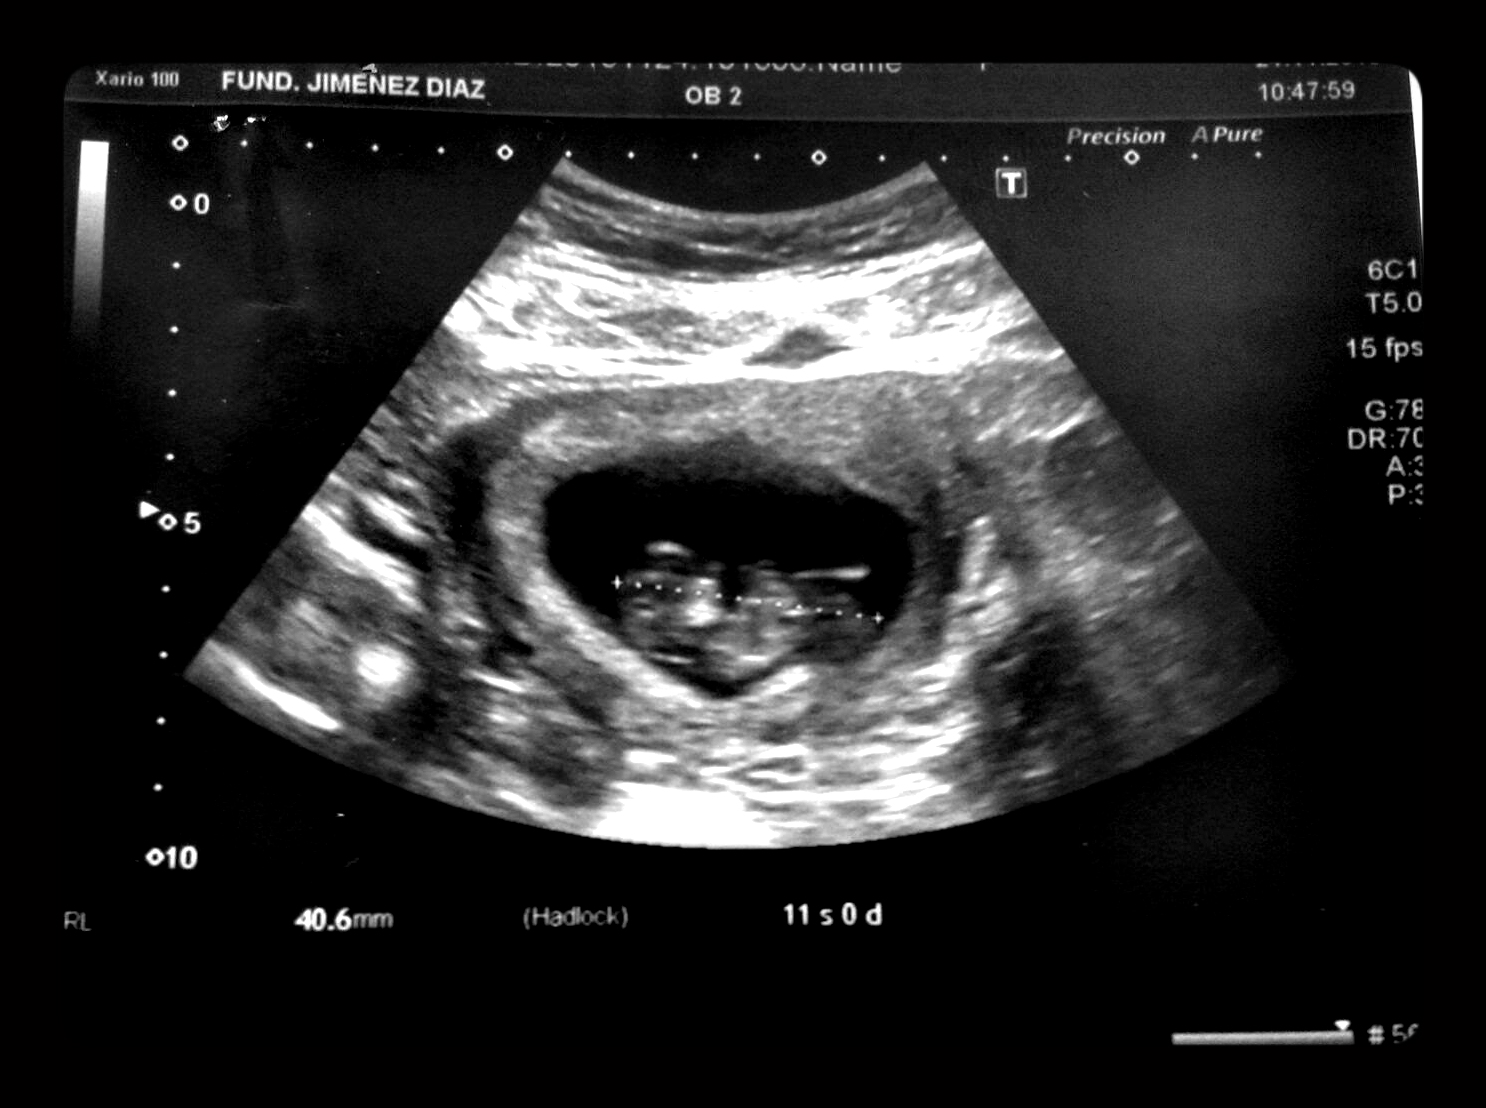

El 12 de Octubre a las 8 de la mañana tuvimos la primera confirmación: habemus alien.

A los pocos días llegó el primer avistamiento. Poco antes de los dos meses, segundo impacto visual.

Así que ahí está nuestro bebé de Schrödinger (no sabemos si es él o ella o ello o qué).